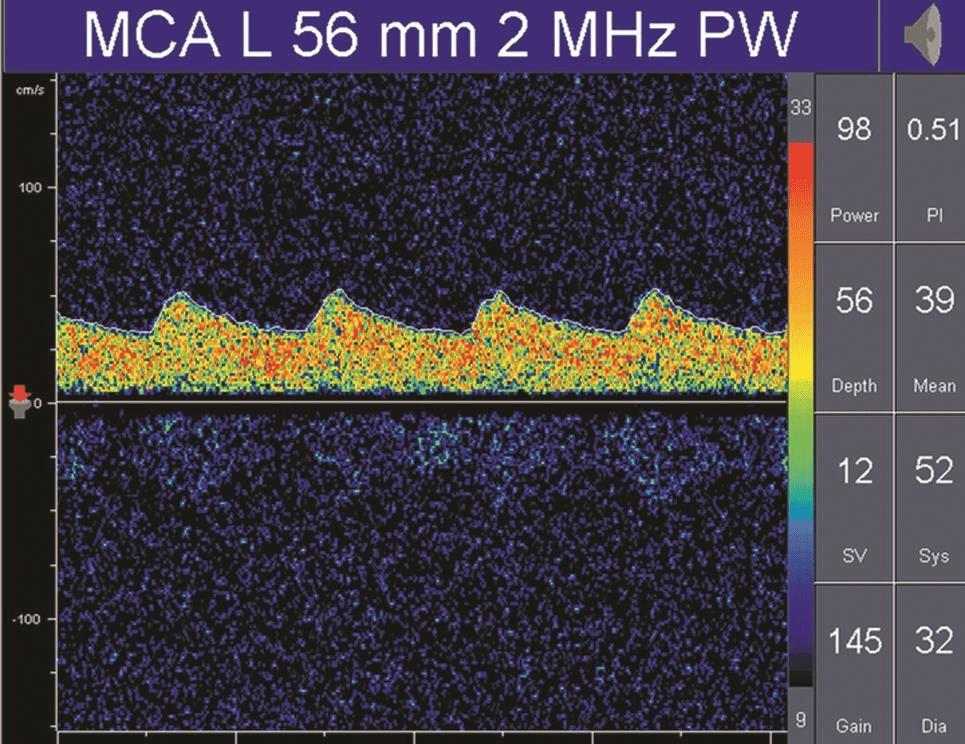

搏動指數(shù)(pulsatility index,PI)和阻力指數(shù)(resistant index,RI)是描述頻譜形態(tài)的參數(shù),通常是由血流速度計算出來,計算公式為:PI=(Vs-Vd) /Vm,RI=(Vs-Vd) /Vs。

PI值主要受收縮期和舒張期血流速度差的影響,差值越大,PI值越大;差值越小,PI值也越小。

因此,PI值可以反映血管內(nèi)血流壓力灌注情況或遠端血管的阻力大小。

正常情況下顱內(nèi)血管的血流頻譜為相對低搏動性波形(PI值為0.55~1.05),而外周血管(顱外頸動脈或肢體血管)為相對高搏動性或高阻力波形(PI值通常大于1.05),顱內(nèi)正常搏動指數(shù)和阻力指數(shù)的頻譜(詳情見下圖)。